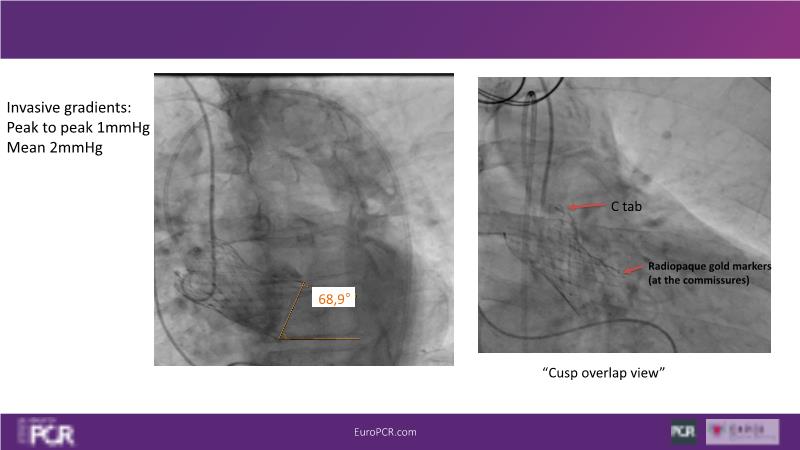

Watch this session to discover insights into patient-prosthesis mismatch and strategies to mitigate risks, delve into the significance of aortic valve commissure for coronary alignment optimization during TAVI, and explore solutions for common TAVI challenges such as peripheral vessel tortuosity and asymmetric valve calcifications in large or small aortic annuli.

- To learn about the importance of aortic valve commissure to coronary alignment and how to control valve implantation to optimise this aspect of TAVI

- To discuss options to overcome common daily challenges of TAVI: peripheral vessel tortuosity, horizontal aorta, asymmetric valve calcifications in large, or in small aortic annuli